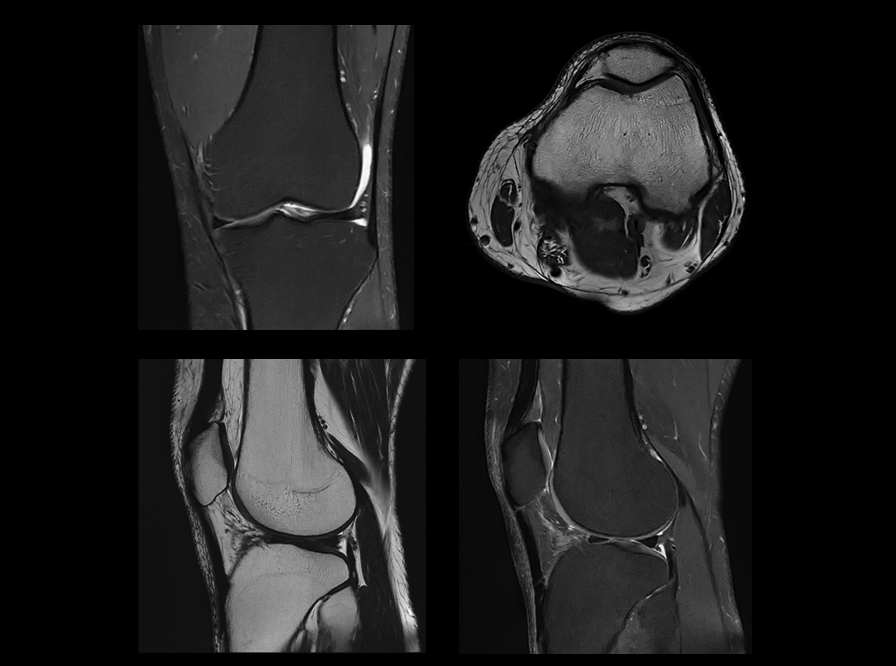

搭载uAIFI Technology技术平台,凝聚多项全球首创核心技术,全链条革新磁共振硬件、软件设计,实现系统性能、扫描智能化、成像速度与信噪比的大幅提升,同时赋予患者更舒适的检查体验,开启磁共振“类脑”时代。

在uMR 880上,我们将全身型磁共振的梯度性能推向了新的高度。更高的梯度梯度性能在弥散扫描时可以帮助用户获得更短的TE时间以提升信噪比同时得到更准确的弥散模型。

新一代数字化射频系统,实现单视野单次扫描最高达72+通道成像。

联影第二代高密线圈,全身成像密度提升超过50%